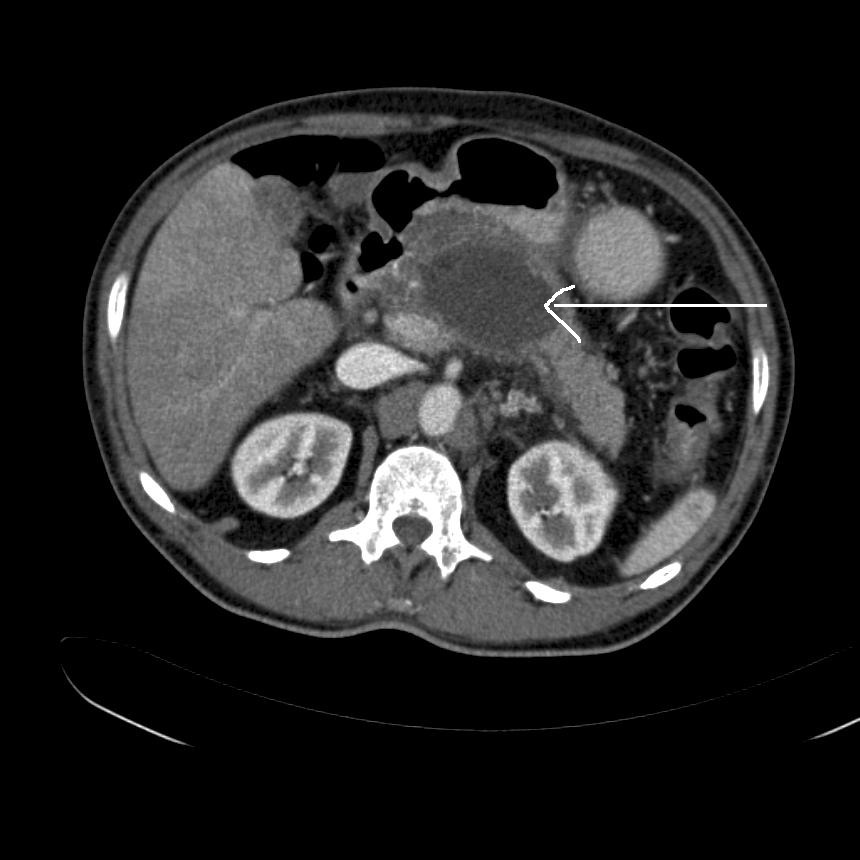

Pankreas, Pseudocyste, CT

Billedet viser en CT-skanning hos en patient med en pseudocyste i pancreas, som i øvrigt ikke har inflammatoriske forandringer. (Pilen angiver pseudocystens placering).